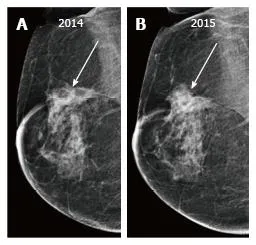

Recurrence Radar - Red Flag Recon

Key: Differentiate recurrence from benign changes.

General Red Flags:

- New/growing mass/density.

- Architectural distortion developing >2 years post-op.

Differentiating Benign Changes:

- Scar: Stable/retracts over time. Initial distortion possible.

⭐ Architectural distortion at the lumpectomy site developing >2 years post-treatment is highly suspicious for recurrence.

- Baseline mammogram post-treatment (lumpectomy/radiation) is crucial at 6-12 months.

- Differentiating scar (stable/shrinks) from recurrence (grows, new calcifications) is key.